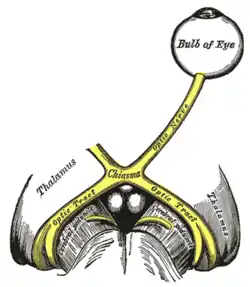

Optic nerves, chiasm, and optic tracts | |

Scheme showing central connections of the optic nerves and optic tracts.